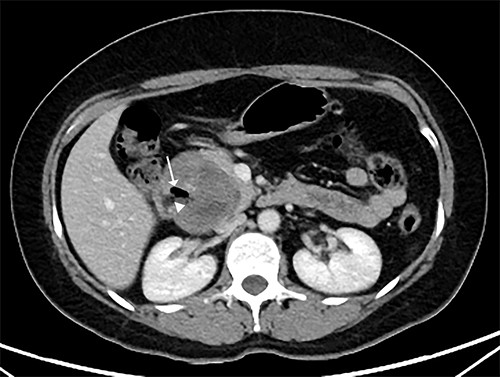

Two months later, she was scheduled for surgical treatment because of the SARS CoV2 pandemic peak. A new CT scan revealed a persistent 6 cm mass in the head of the pancreas, now containing air and communicating with the duodenal lumen (Fig. 3). A slight decrease in volume was also noted. The patient underwent a pancreatoduodenectomy with standard lymphadenectomy. The procedure took 240 min and involved 200 mL of blood loss. The patient was discharged 8 days postoperatively without complications. The histopathological examination showed a neoplasm of the head of the pancreas, with a solid and cyst appearance, and abundant haemorrhagic content. The neoplasm extended to the duodenum, causing fistulation to the lumen (Fig. 4). The immunohistochemical study showed expression of β-catenin, synaptophysin, vimentin and progesterone receptor (15%) and negativity for chromogranin, E-cadherin and CD117 (Fig. 5). The labelling index of Ki 67 was 2%, and the final diagnosis was a T3N0M0 SPN. The patient did not receive postoperative chemotherapy and has remained symptom-free with no detectable recurrence for 2 years of follow-up.

CT scan showing that tumour reduced to 6 cm, containing an air cavity (white arrow) and communicating with the duodenal lumen (arrowhead).